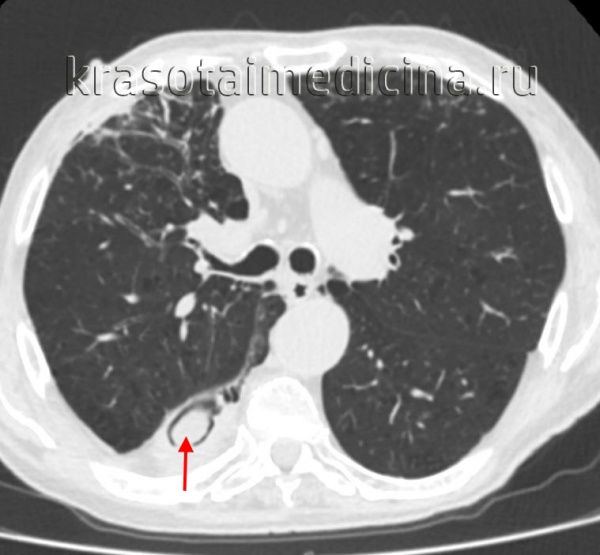

Для ингаляционных поражений характерны поражения респираторного тракта.

Продолжительное течение болезни способствует возникновению деструктивных изменений в костях и мягких тканях, инвалидизации больного. Наиболее частыми осложнениями патологии являются остеомиелит, артрит, тендовагинит, флегмоны, абсцессы, сепсис. Наличие очага хронического воспаления в организме может в перспективе приводить к амилоидозу внутренних органов. Локализация процесса на нижних конечностях предрасполагает к тромбоэмболическим осложнениям. При глубокой иммунодепрессии, СПИДе иногда наблюдается фунгемия и бактериемия с формированием гнойных очагов во внутренних органах. Возможен эндокардит, эндофтальмит.